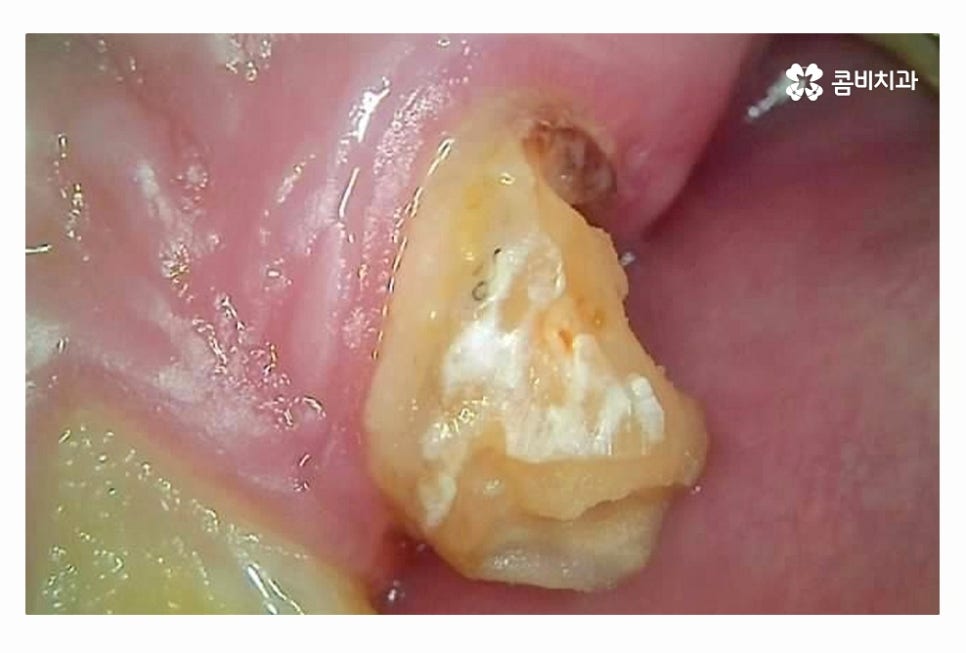

충치로 인해 치아를 잃게 되는 대표적인 사례라면

이미 과거에 치료를 했거나 치아 사이처럼 눈에 잘 띄지 않는 부위에

충치가 심해져서 치수 혹은 치아의 뿌리까지 손상이 심해진 경우라고 할 수 있어요.

충치는 누구나 발생할 수 있고 과거에 레진이나 인레이 등의 치료를

했던 분들이라면 시간이 지날수록 주변 치아 혹은 치료에 쓰인 재료가

손상, 마모 등을 거치게 되는데 치아 속에 2차 충치가 발생하는 경우에는

그로 인한 치아 손상이 심각한 상황으로 커지는 경우가 많다고 할 수 있어요.